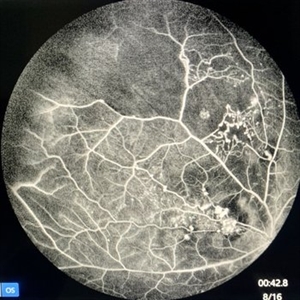

Vascular Anormalities

77-year-old man. Decrease of visual acuity OS. VA 20/30 IOP 14mmHg. Fundus examination findings: Hard exudates, microaneurysms near to fovea. OCT shows IRF. Late leakage on FA.

Photographer: Andrea Elizabeth Arriola-Lopez, MSc MD

Condition/keywords: abnormal retinal vessel, aneurysm, hard exudates, vascular anomaly